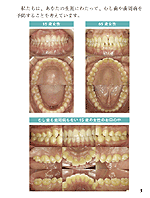

<I>は口腔内写真を応用してつくる、口腔衛生指導料と衛生士実地指導料の二つの算定要件を兼ね備えた提供文書です。

<II>は歯周疾患指導管理に活用できるプリントです。患者さんのお名前・歯科医院名・担当歯科衛生士名をいちいち入力する必要はありません。